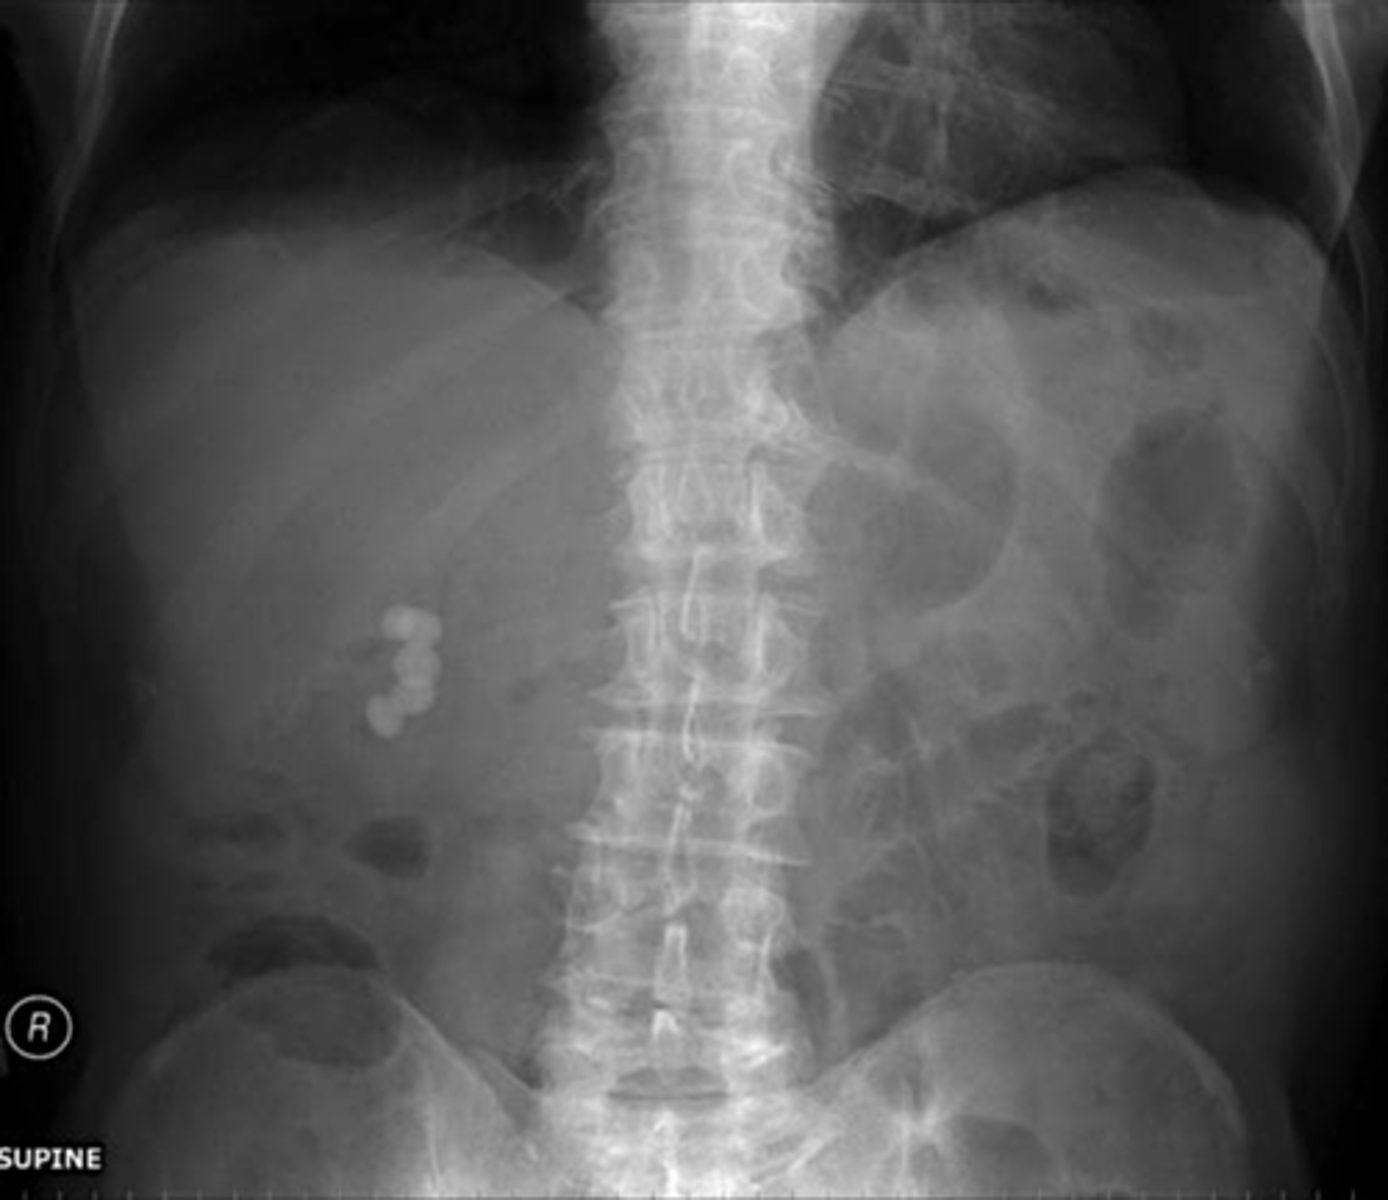

Kidney stones

Kidney stones (pic 2)

kidney stones (pic 3)